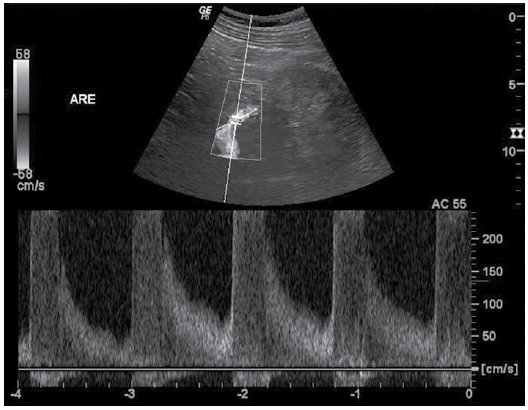

Considere a seguinte situação: paciente, sexo masculino, 73 anos, com história de hipertensão arterial sistêmica de difícil controle medicamentoso. Foi solicitado doppler das artérias renais.

As figuras a seguir mostram o achado de imagem mais relevante na artéria renal esquerda.

Analise as alternativas a seguir, e assinale aquela que melhor interpreta o exame doppler das artérias renais.